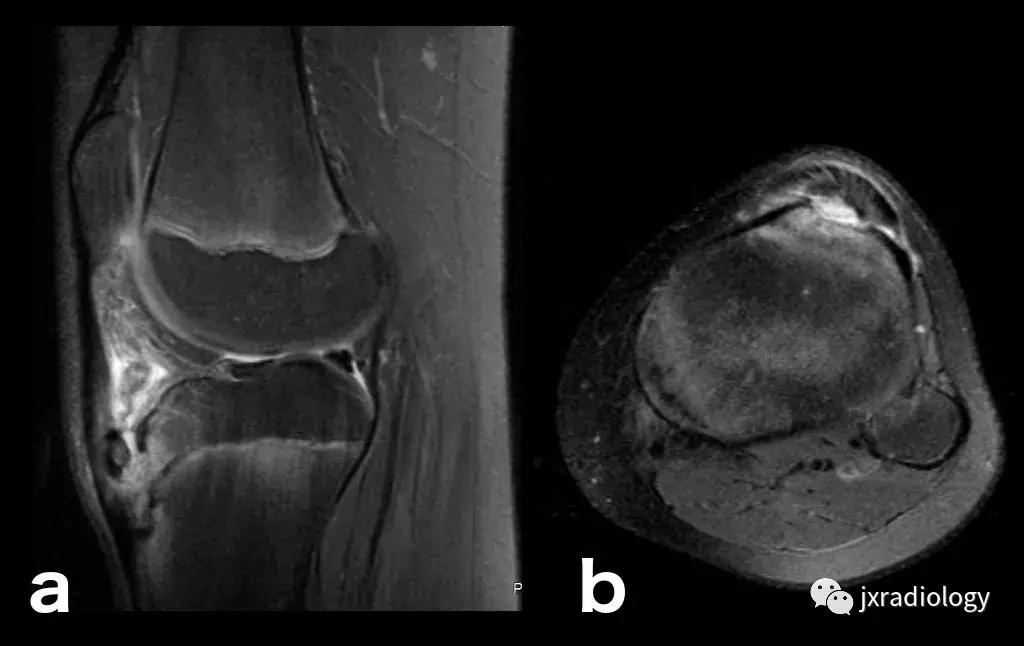

图28:正常的红骨髓:这是寻找骨髓水肿时可能出现的误区。造血系统红骨髓(由于年轻患者正常分布或成人骨髓再生)在T1-WI(b)和水敏序列(a:PD-FS-WI)上均具有中等信号强度。T1-WI上的正常红骨髓相对于肌肉的分布(通常在干骺端)的特征性模式和较高的信号强度(与T1-WI上肌肉组织的等信号或低信号的病理性骨髓相反),应能及时发现这一正常发现。